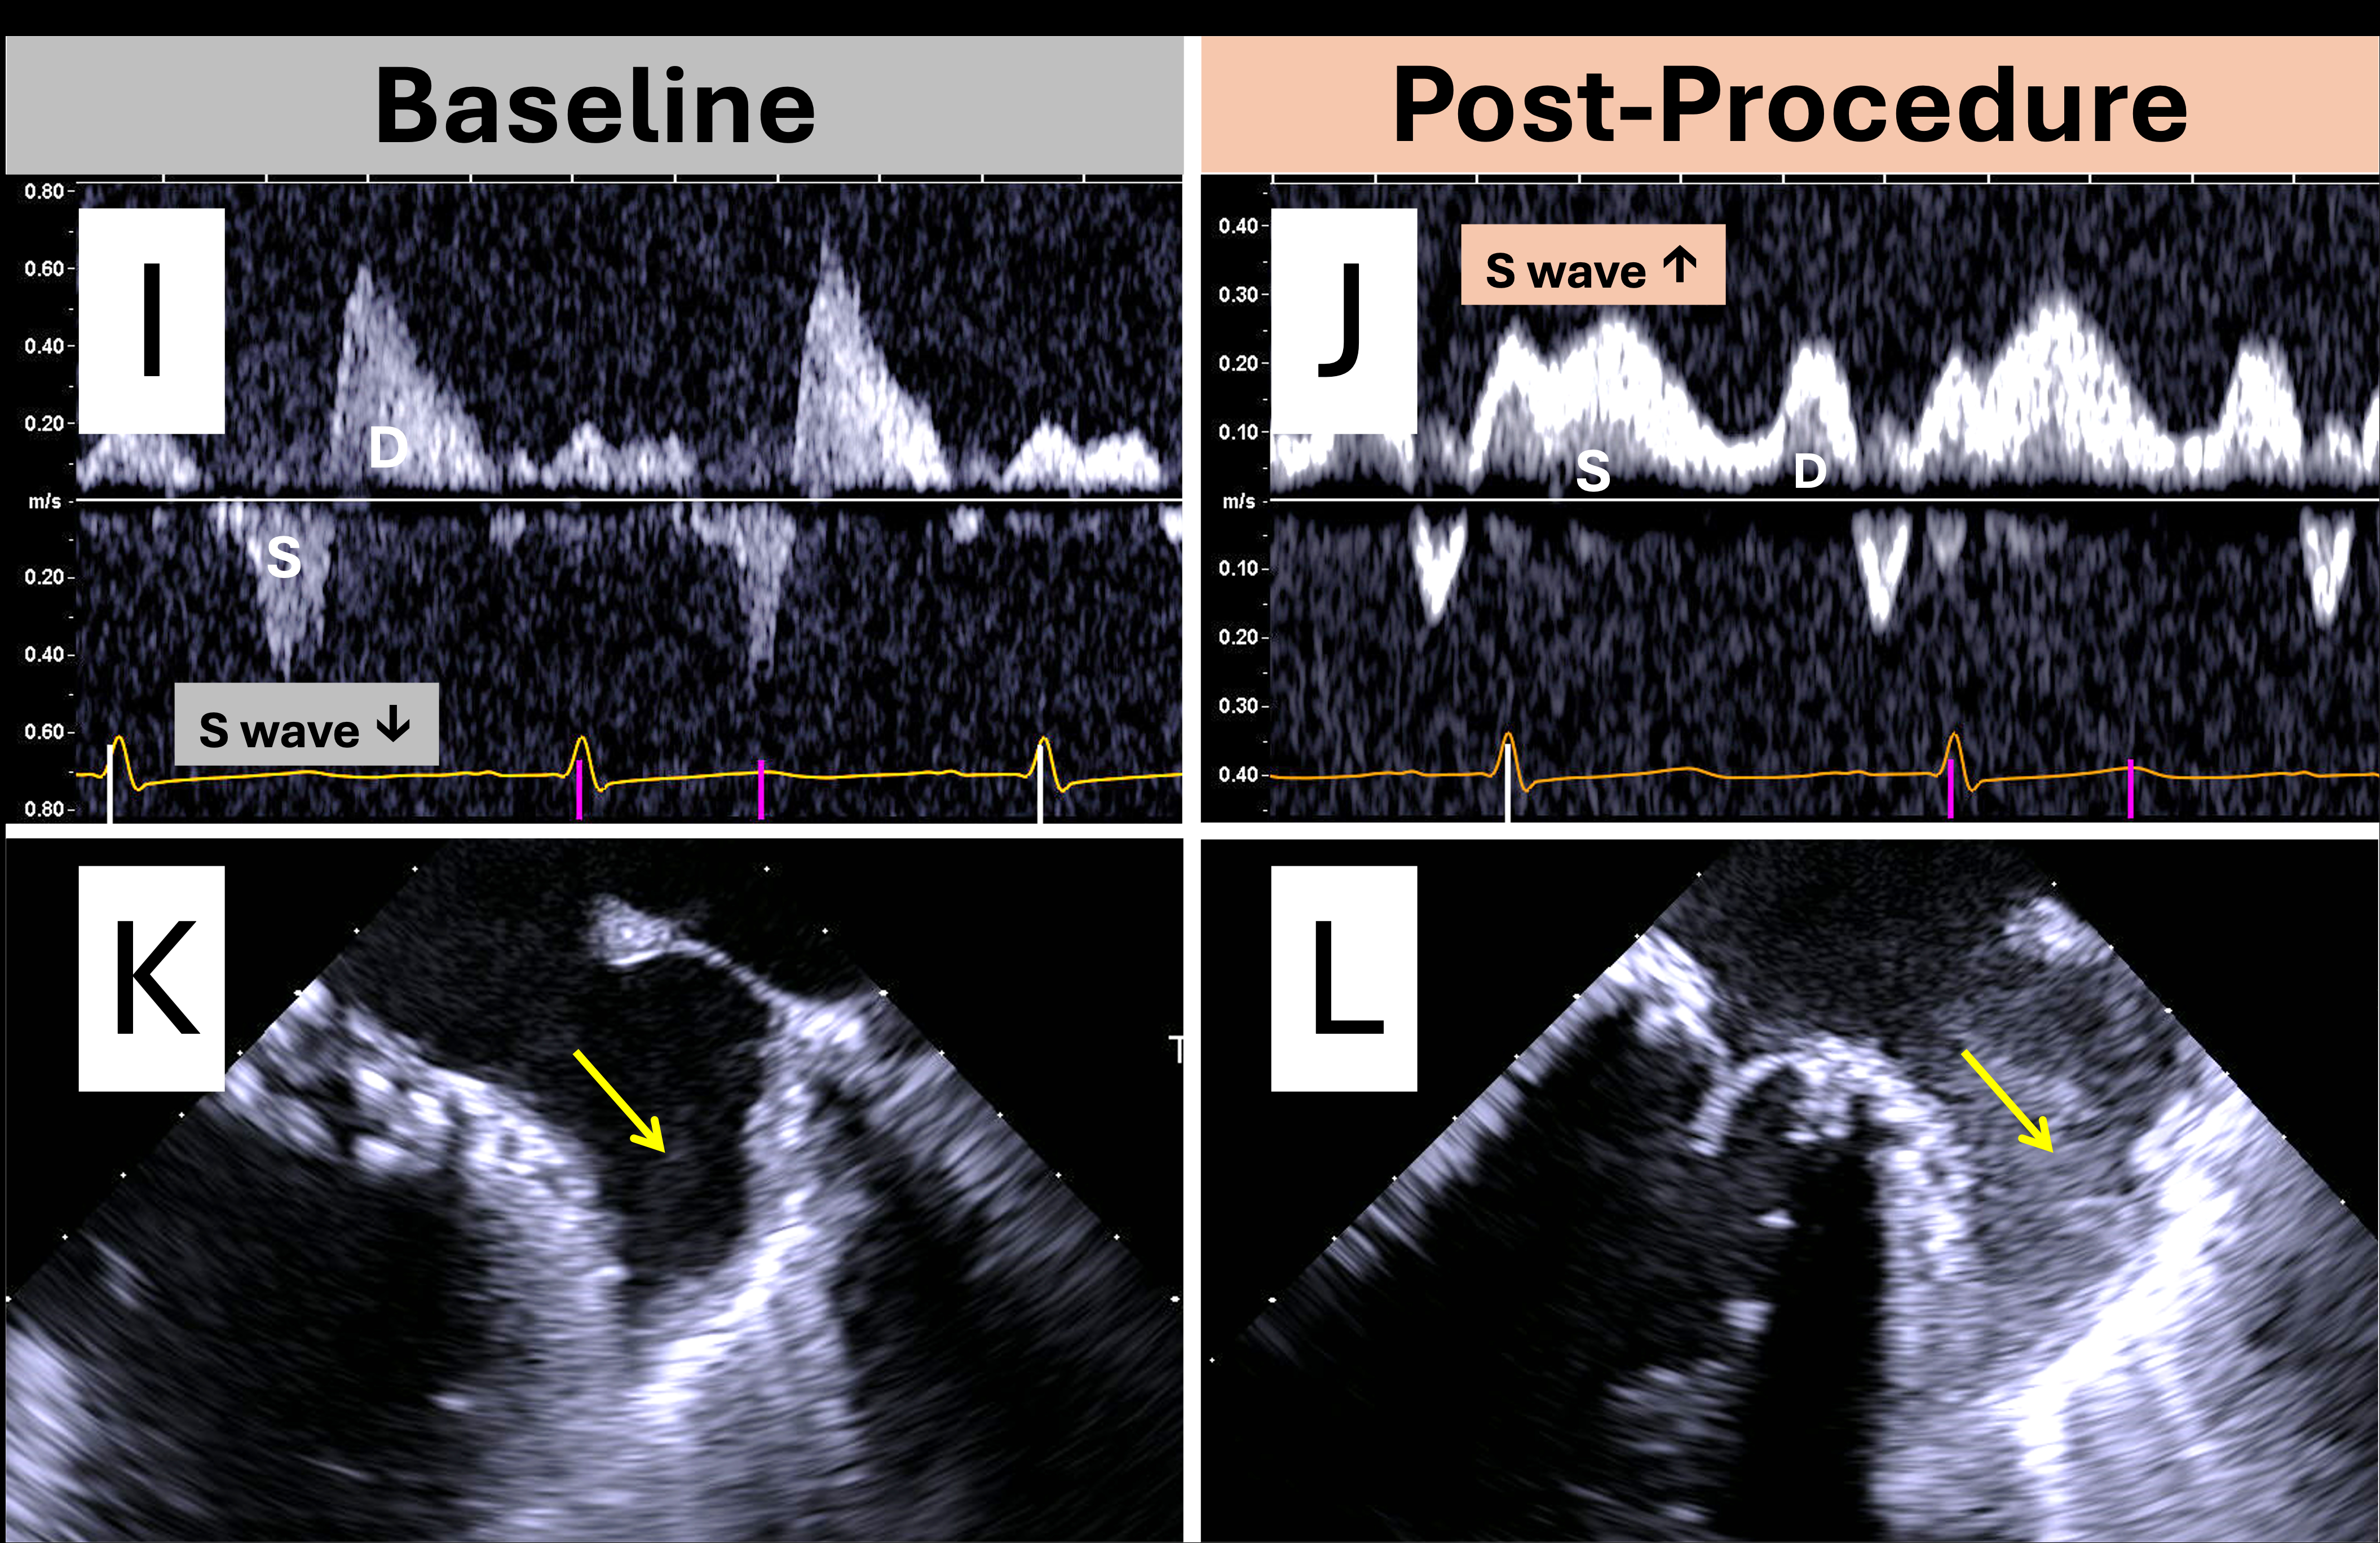

Case 3: An 82-year-old woman with degenerative MR showed an E-wave dominant mitral inflow pattern with slow deceleration and pulmonary S wave reversal in the right upper pulmonary vein (RUPV). After TEER, the inflow pattern became A-wave dominant, and S wave reversal resolved.

Key echocardiographic indicators of resolved severe MR post-intervention include: (1) marked reduction in jet area on color Doppler, (2) increased LVOT stroke volume indicating improved forward flow, (3) transition from a dense, low-Vmax, triangular MR jet contour to a less dense, high Vmax, parabolic MR jet contour on spectral Doppler reflecting improved LA hemodynamics, (4) decreased transseptal pressure gradient across the iatrogenic ASD reflecting improved LA pressure, (5) shift from E-wave to A-wave dominant mitral inflow in the absence of significant mitral stenosis, (6) return of antegrade pulmonary S wave flow reflecting decreased LA pressure, and (7) reappearance of LAA SEC, as the MR jet no longer washes away the SEC seen in chronic atrial fibrillation. While no single measure is definitive, these findings support a multimodal approach to residual MR assessment and highlight the need for further validation.